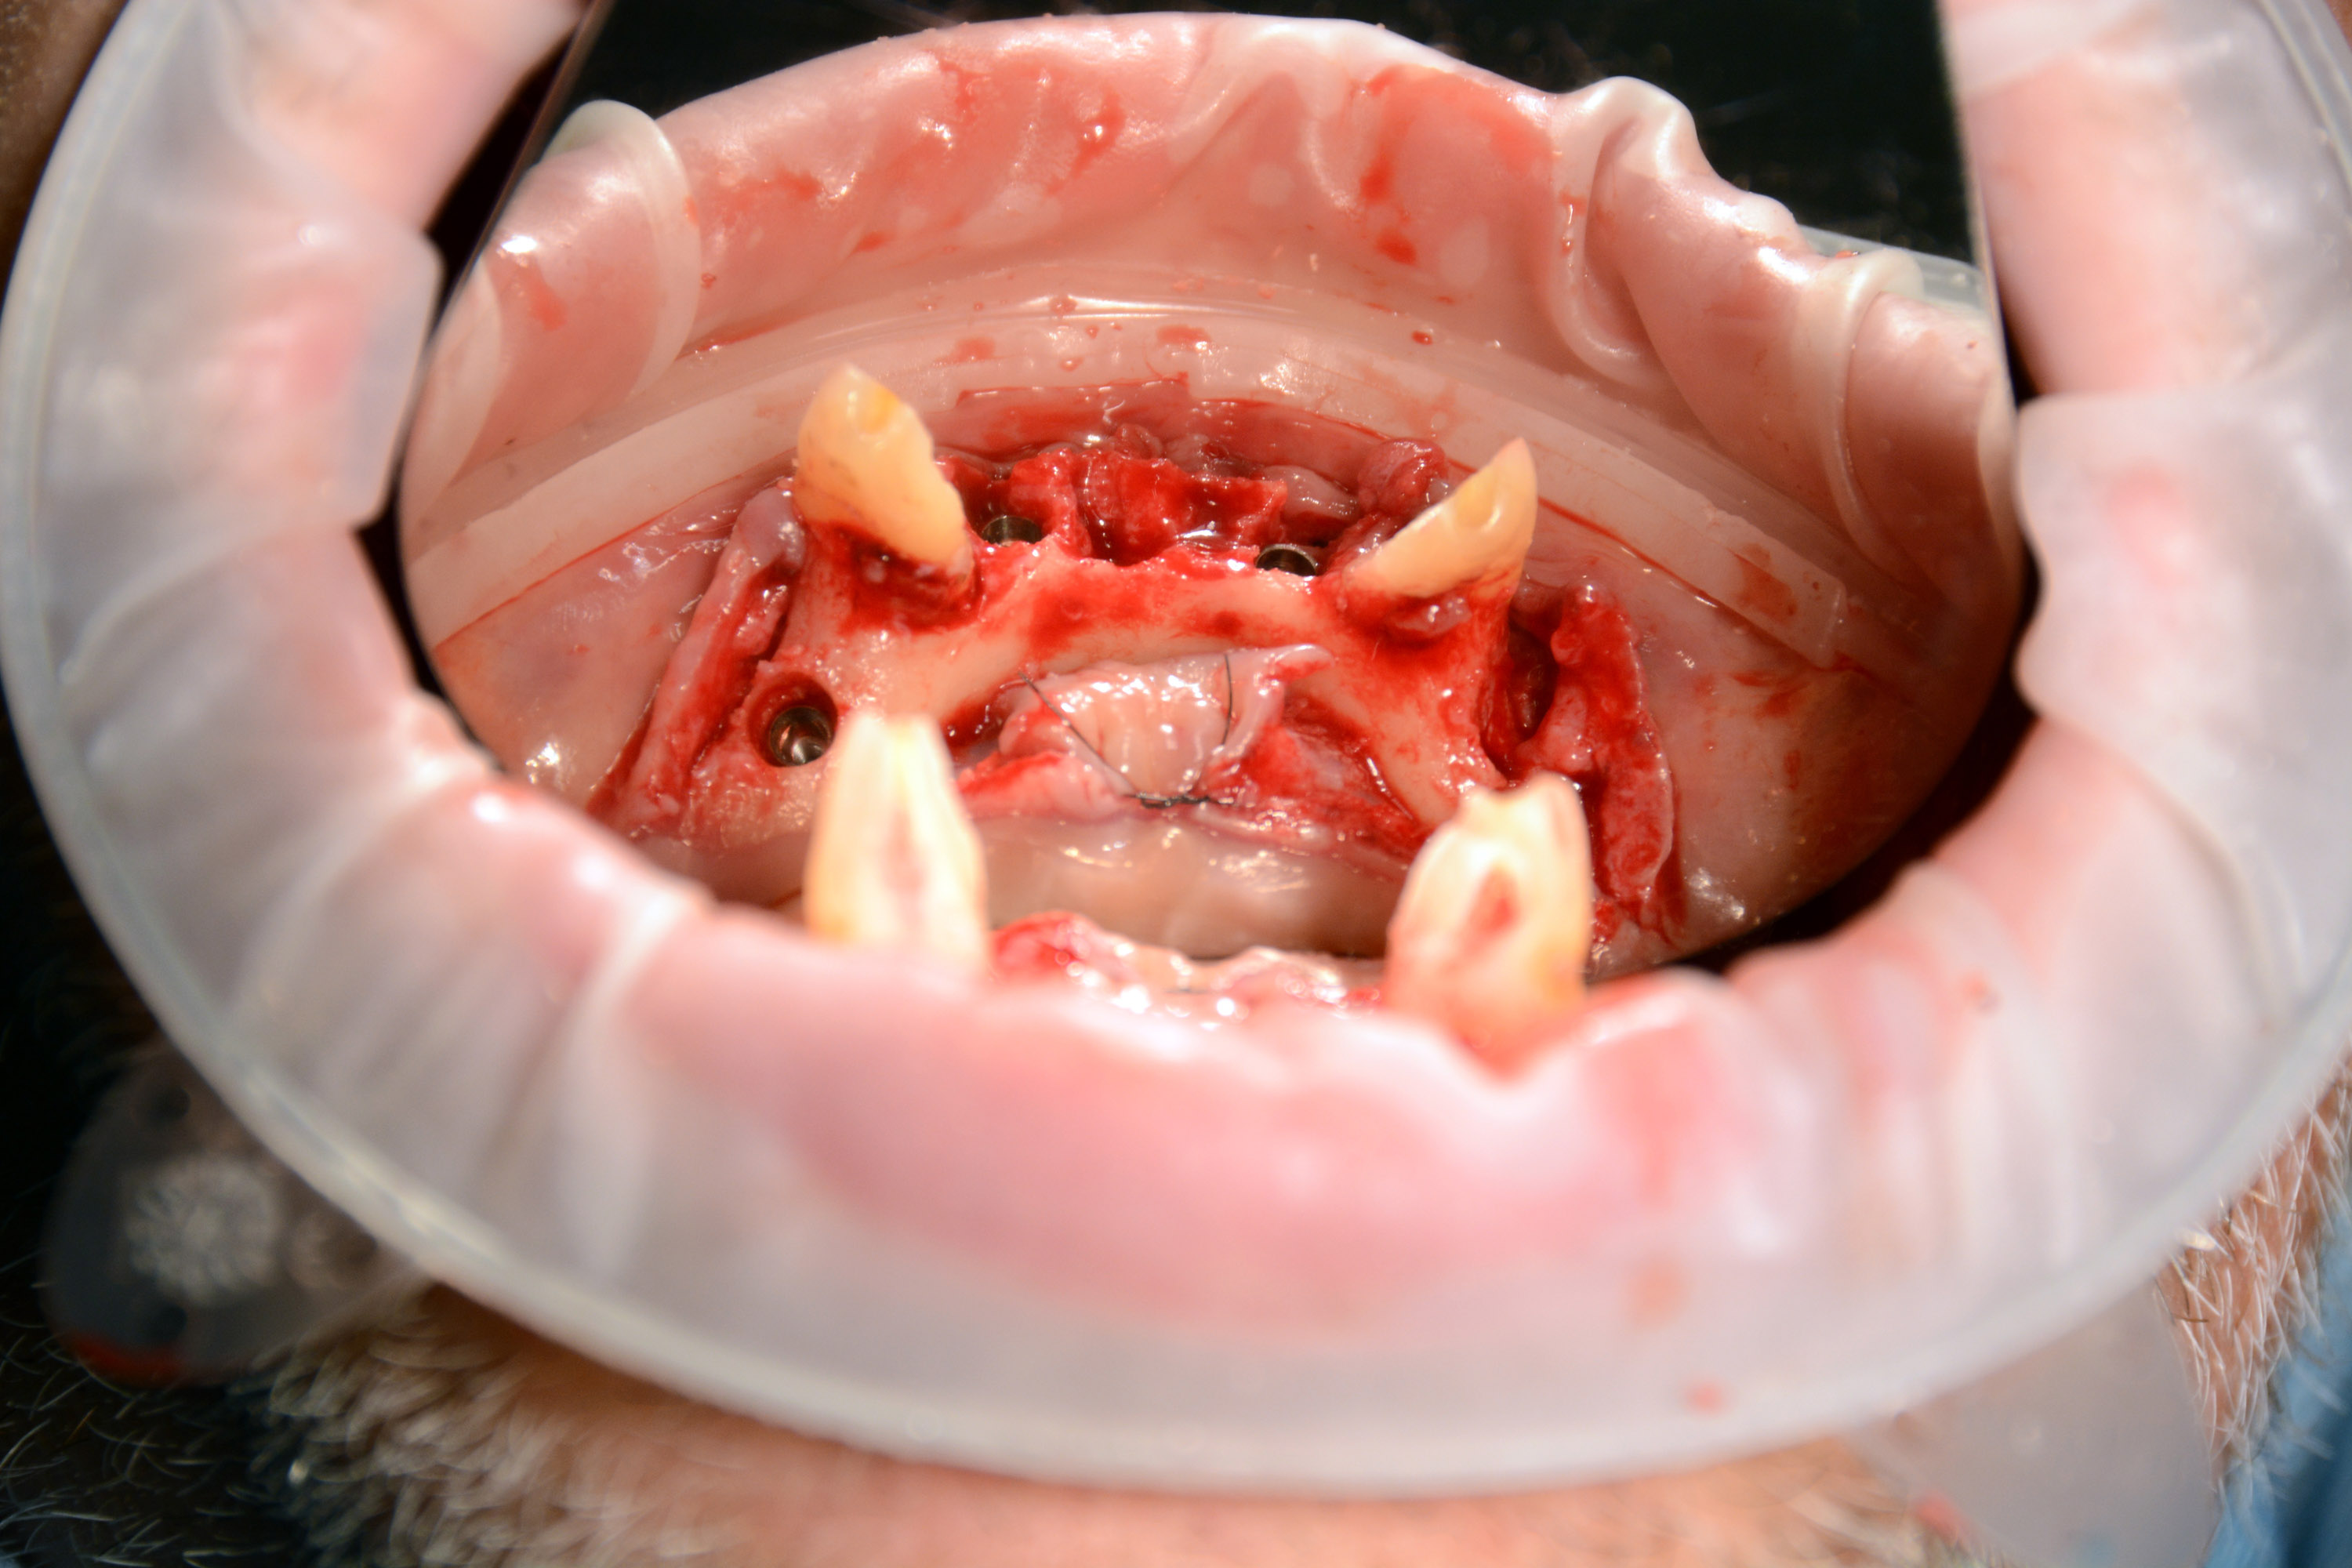

Pierwszy zabieg polegał na usunięciu 6 zębów w żuchwie i wprowadzeniu 4 implantów z wykorzystaniem szablonu chirurgicznego do pełnej nawigacji. Bezpośrednio po zabiegu zostały przykręcone multiunity do implantów i osadzony tymczasowy most.